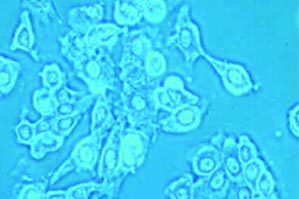

Do you see where this is going yet? The group sifted through a huge library of protein-tagged bacteriophages until they found one that was recognized by breast cancer cells. Then they mixed the phage-derived protein with a the nanocarrier containing a drug that kills breast cancer cells. The bacteriophage lodged itself inside the nanocarrier’s lipid membrane, as if it were a bacterial membrane, with the protein fragment dangling on the outside. Then they mixed these little guys with cancerous and non cancerous cells in a test tube and found that they attacked cancer cells and bypassed healthy cells.

A foregin gene inserted into the bacteriophage (left) tags it with a protein fragment, which is recognized by receptors on the surface of a cancer cell but not a healthy cell. The tagged bacteriophage spontaneously nestles into the lipid membrane of the drug-containing nanocarrier (right).